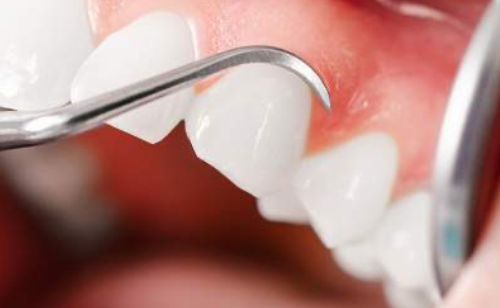

歯肉炎や歯周病になっていないか検査をします。歯と歯茎の間を触って確認し記録していきます。

歯肉炎・歯周病を診るための検査です。定期検診では、歯周病の治療にて炎症が落ち着いた場所の経過を診たり、新しく炎症を起こしていないか診ていきます。